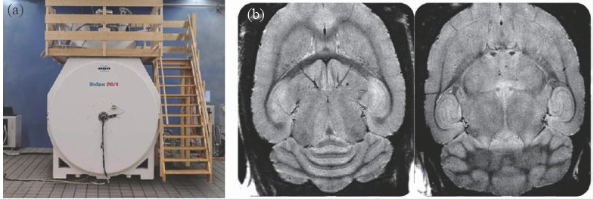

除了人体成像的超高场磁共振成像装置外,用于动物临床前应用的装置在磁场强度上远远走在了前面,10 年前就出现了16.4 T/26 cm动物成像MRI 机,德国的Bruker公司在几年前也推出了更高磁场的动物成像机—— 21 T/11 cm动物成像MRI机(图8)。

图8 (a)21 T MRI磁体;(b)大鼠的脑部高分辨率成像(分辨率26 μm)